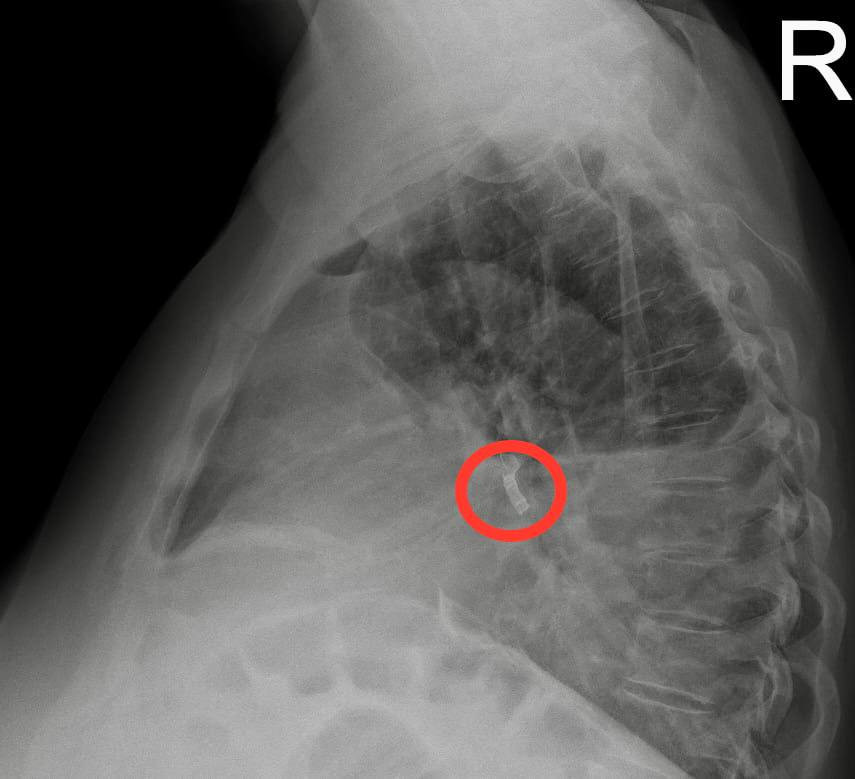

В ходе диагностики в НИИ имени Джанелидзе выяснилось, что в промежуточном бронхе справа находится инородное тело – его было видно на рентгеновском снимке и на КТ. Оказалось, что около года назад женщина во сне вдохнула часть зубного протеза. Не найдя эту часть, она решила, что где-то её потеряла.

Металлический предмет, пробыв в бронхе около года, вызвал гнойное воспаление плевральной полости. Инфекция попадала в плевральную полость из лёгкого через образовавшийся свищ.

Зубной протез длиной около полутора сантиметров из бронха пациентки извлёк Муса Сафоев, заведующий эндоскопическим отделением отдела неотложной хирургии, кандидат медицинских наук.